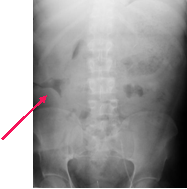

There is a “pad sign” (extrinsic impression) on the loop of bowel in

the RLQ. This is caused by a soft tissue mass impressing the bowel

from outside. The CT shows an abscess from a ruptured appendix.